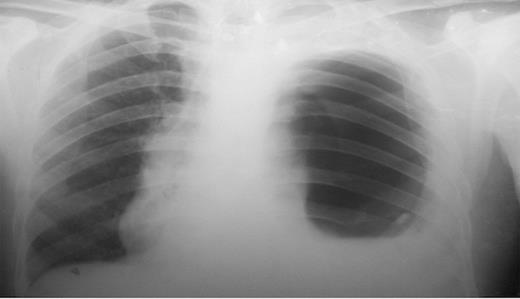

The presence of the nasogastric tube was confirmed with the presence of gurgling sound on auscultation after administration of air through it. Barium meal was carried out to localize the stomach and showed the presence of the stomach in the thoracic cavity confirming diagnosis of post-traumatic diaphragmatic hernia. (Figure 2)